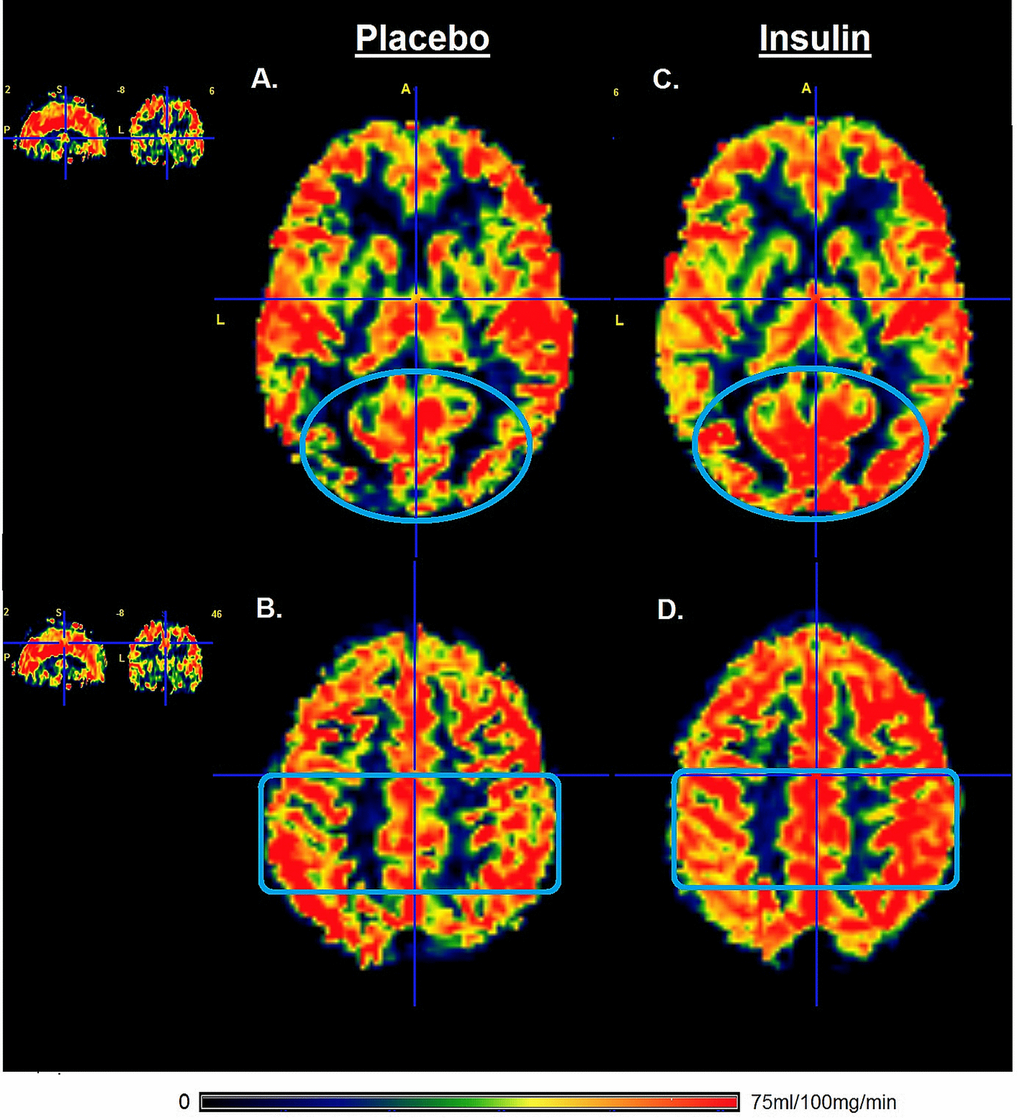

In older adults, intranasal administration of insulin significantly increased perfusion through the occipital gray matter with 6.5% when compared to the administration of placebo (Table 3, P=0.001). Perfusion through the parietal gray matter was 4.3% increased after intranasal administration of insulin (P=0.034). Perfusion in the frontal and the temporal gray matter regions was not significantly changed after intranasal administration of insulin (Table 3). In older adults, intranasal administration of insulin significantly increased perfusion in the thalamus (P=0.003), but no significant changes were found for perfusion in the hypothalamus. After application of Bonferroni corrected significance threshold of P<0.007, only the changes in occipital grey matter and the thalamus remained significant. The change in perfusion after intranasal application of insulin for one representative participant is visualized in the gray matter perfusion map shown in Figure 2.

Figure 2. Gray matter perfusion maps after intranasal administration of placebo and insulin. Left panel (A and B) represents the gray matter perfusion map after intranasal placebo administration and the right panel (C and D) the perfusion map after intranasal insulin administration for one representative older participant. The top row shows an increase in the gray matter perfusion of occipital lobe (illustrated by blue oval) after intranasal administration of insulin compared to placebo. The bottom row shows an increase in gray matter perfusion in the parietal lobe (illustrated by blue rectangle) after intranasal administration of insulin compared to placebo. Only the gray matter was included for calculation of perfusion after intranasal administration of insulin compared to placebo.